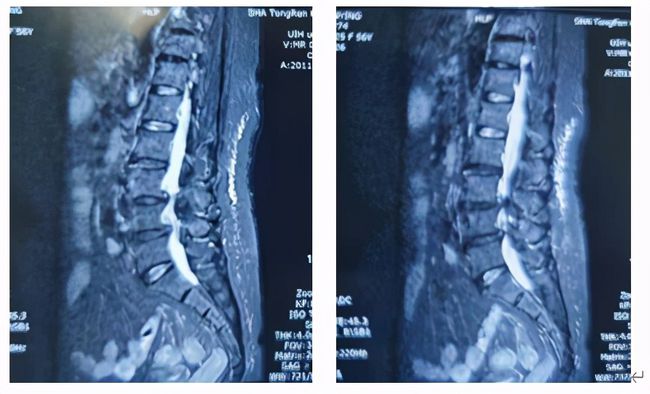

近期,邵女士前往上海交通大学医学院附属同仁医院脊柱外科就医,X线检查,腰4椎体轻度滑脱并有退变性侧弯,MR检查提示椎间盘突出,椎管明显狭窄,黄韧带肥厚、硬膜囊及神经根受压,诊断为:腰椎滑脱伴椎管狭窄症。

手术团队充分讨论,患者诊断明确,需手术解除椎管狭窄及恢复腰椎稳定。传统开放手术可以解决问题,但创伤较大,出血会较多,同时患者身体较差,存在一定风险。与患者沟通后,邵女士希望能微创手术治疗,最后决定行微创OLIF+内镜手术

本病例患者L3/4存在腰椎滑脱、椎间隙高度丢失;但L4/5椎间隙高度丢失不明显,所以选择了L3/4、L4/5两个节段的OLIF同是进行L4/5的内镜手术(OLIF+内镜),充分的结合了两种术式的优缺点,是间接减压与直接减压的完美结合。所以对于严重的椎管狭窄或滑脱也是可以采用微创的方式来解决的。目前国内开展此类微创手术鲜有报道。